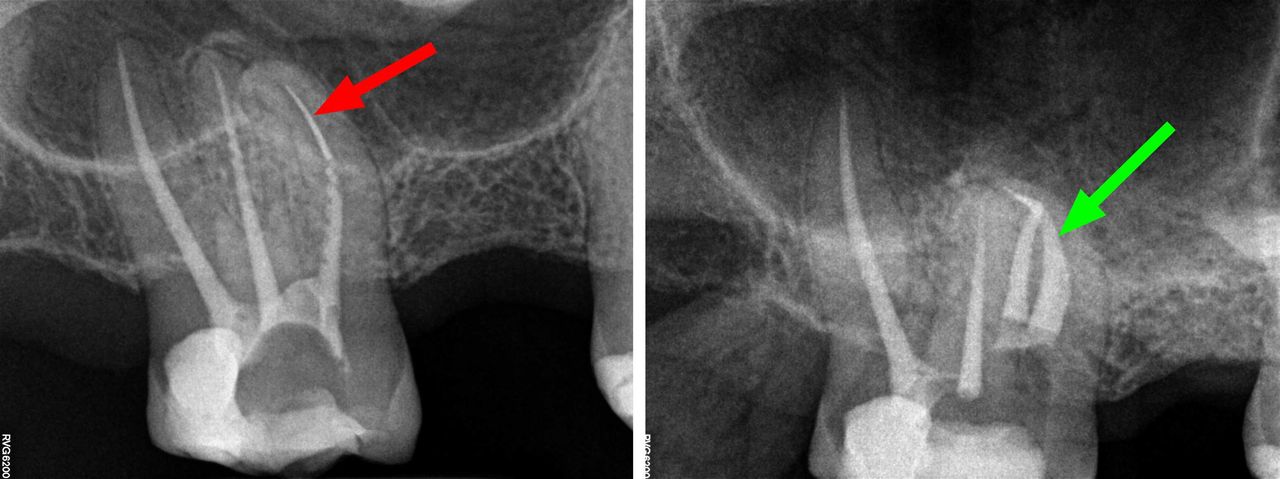

- Usuwanie złamanych narzędzi kanałowych oraz innych ciał obcych pozostawionych w kanałach korzeniowych

- Specjalizujemy się w powtórnym leczeniu kanałowym i leczeniu powikłań co oznacza, że mamy wieloletnie doświadczenie w usuwaniu złamanych instrumentów kanałowych w szybki, bezbolesny i nieinwazyjny sposób. Dr Gończowski jest autorem specjalistycznego zestawu mikroinstrumentów (FRS®) przeznaczonych do usuwania ciał obcych z kanałów korzeniowych